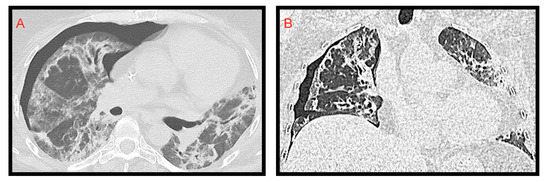

Figure 10. (AC): A 14-year-old girl with spontaneous pneumothorax and pneumomediastinum, in association with extensive ground glass changes. In Figure 10C consolidation of the right lower lobe is noted.

3.5. Pneumothorax and Pneumomediastinum

Spontaneous pneumothorax and pneumomediastinum (Figure 10) are also very infrequent findings in pediatric COVID-19-related pneumonia: a study [27] reported pneumothorax in 2% of cases, and a few case reports in the literature have described these findings [33,34], usually in adolescents with severe disease.